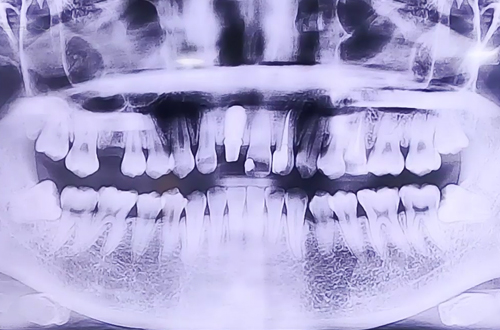

부러진 앞니 임플란트

AFTER

야간진료 시간에 앞니가 부러져 급하게 내원해 주셨던 환자분이십니다.

처음엔 자연 치아를 최대한 살리는 방향의 치료를 고려했지만 치아 상태가 그러기 어려워 부러진 앞니를 발치하고 임플란트를 통해 복원하는 방향으로 치료를 진행중이십니다.

현재 식립한 임플란트가 제대로 자리 잡을때까지 임시 치아를 제작해 씌워드린 상태이며, 추후 임플란트가 단단히 자리 잡고 보철이 완성되면 다음 진료일지로 찾아뵙도록 하겠습니다. ^^